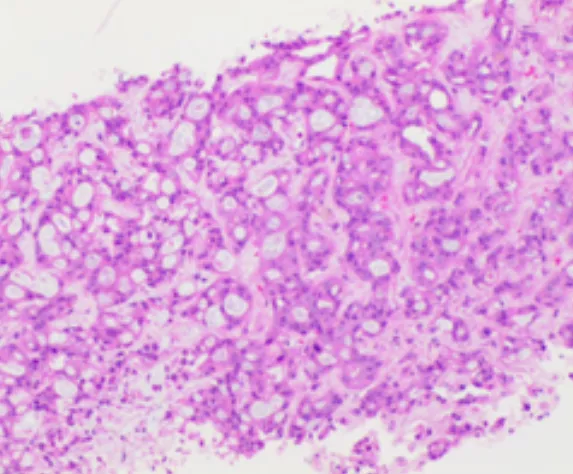

肝內(nèi)病灶穿刺組織病理結(jié)果

(肝內(nèi)病灶穿刺組織)肝組織內(nèi)見(jiàn)腺癌浸潤(rùn),免疫組化結(jié)果:CK7(+),CK19(+),Ki-67(約30%+),P53(彌漫強(qiáng)+),CEA(部分+),TTF-1(-),結(jié)合病史及影像學(xué)檢查,首先考慮胰腺癌轉(zhuǎn)移。